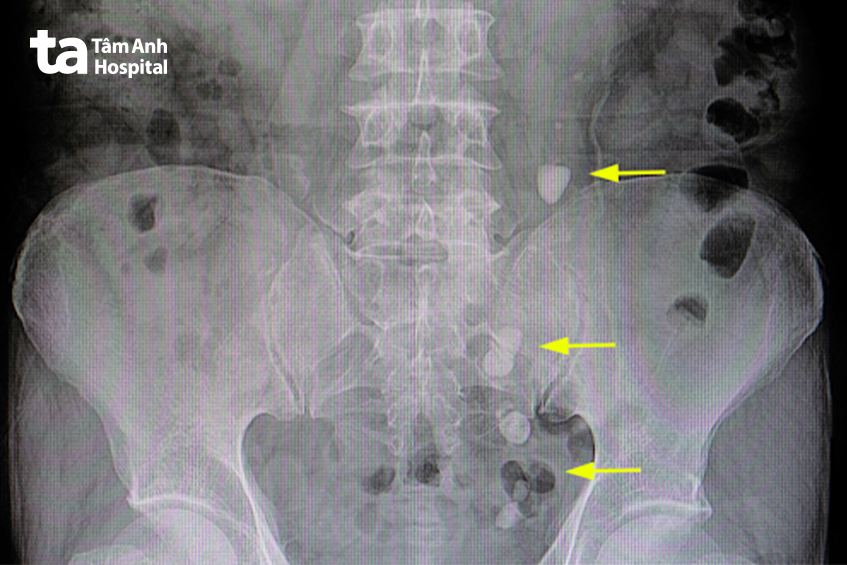

Hình chụp X-quang sỏi niệu quản.